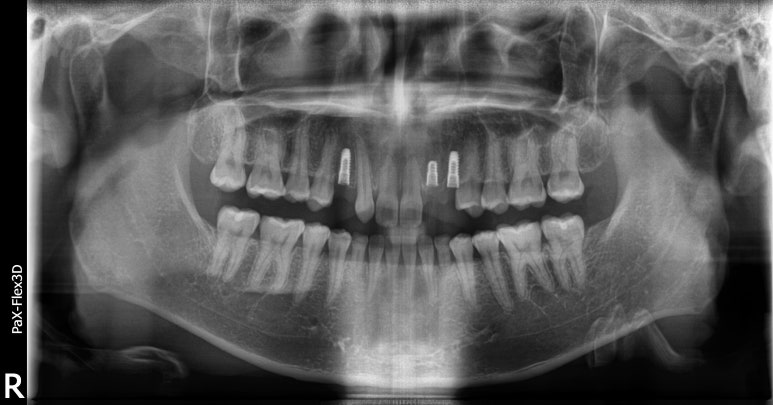

디데이치과 네비게이션임플란트 시술 전, 시술 중 엑스레이 사진

위 환자분은 앞니에 임플란트를 식립하신 환자분이라 조금 더 세밀한 식립이 가능한 네비게이션 임플란트로 수술을 진행하셨습니다.

이처럼 보다 섬세하고 세밀한 식립이 필요한 치아에 임플란트 수술을 진행할 경우에도 네비게이션으로 수술을 고려해볼 수 있습니다.